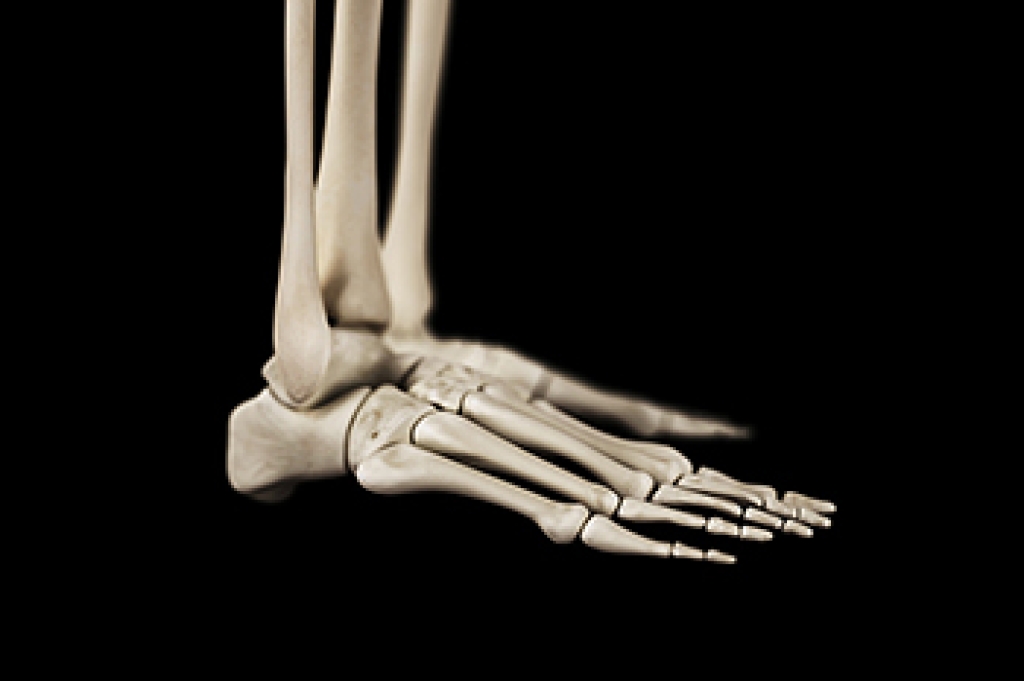

Rheumatoid arthritis, or RA, is an autoimmune condition that causes the immune system to attack the lining of the joints, leading to chronic inflammation. The feet and ankles are commonly affected because they contain many small joints that bear body weight. Persistent swelling, pain, warmth, and stiffness may develop, especially in the morning or after rest. In the midfoot, inflammation can lead to collapse of the arch and difficulty walking. In the hindfoot and ankle, joint damage may cause instability, limited motion, and progressive deformity. Over time, untreated inflammation can significantly affect mobility and quality of life. If you have symptoms of RA in your feet, it is suggested that you consult a podiatrist who can monitor joint health, provide supportive orthotics, and recommend appropriate treatment.

Because RA affects more than just your joints, including the joints in your feet and ankles, it is important to seek early diagnosis from your podiatrist if you feel like the pain in your feet might be caused by RA. For more information, contact one of our podiatrists of Associates in Podiatry, PC. Our doctors will assist you with all of your podiatric concerns.

What Is Rheumatoid Arthritis?

Rheumatoid Arthritis (RA) is an autoimmune disorder in which the body’s own immune system attacks the membranes surrounding the joints. Inflammation of the lining and eventually the destruction of the joint’s cartilage and bone occur, causing severe pain and immobility.

Rheumatoid Arthritis of the Feet

Although RA usually attacks multiple bones and joints throughout the entire body, almost 90 percent of cases result in pain in the foot or ankle area.

Quick diagnosis of RA in the feet is important so that the podiatrist can treat the area effectively. Your doctor will ask you about your medical history, occupation, and lifestyle to determine the origin of the condition. Rheumatoid Factor tests help to determine if someone is affected by the disease.